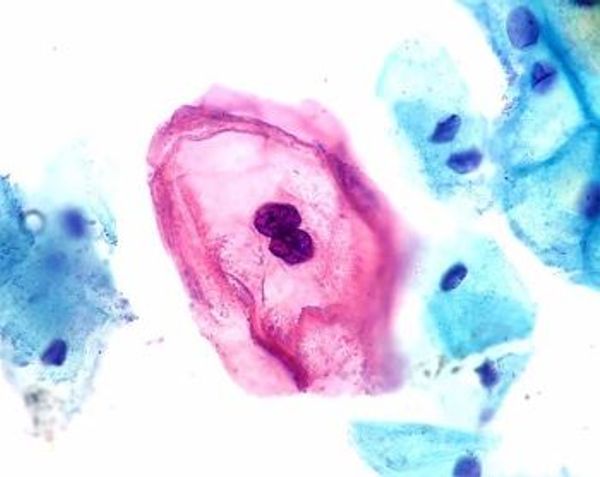

In de meeste gevallen wordt het HPV-virus door het afweersysteem van het lichaam netjes opgeruimd. Maar dat gebeurt helaas niet altijd. Soms – bij 10 tot 20 procent van de mensen die besmet zijn - krijgt het virus grip op gezonde cellen en verandert deze door ze te beschadigen. Zijn er veel cellen beschadigd dan kan dit uiteindelijk uitmonden in een vorm van kanker. Van het HPV-virus bestaan meer dan honderd verschillende types. Deze zijn niet allemaal gevaarlijk of een veroorzaker van kanker. Het zijn met name de HPV-types 16 en 18 die verantwoordelijk zijn voor het krijgen van kanker.